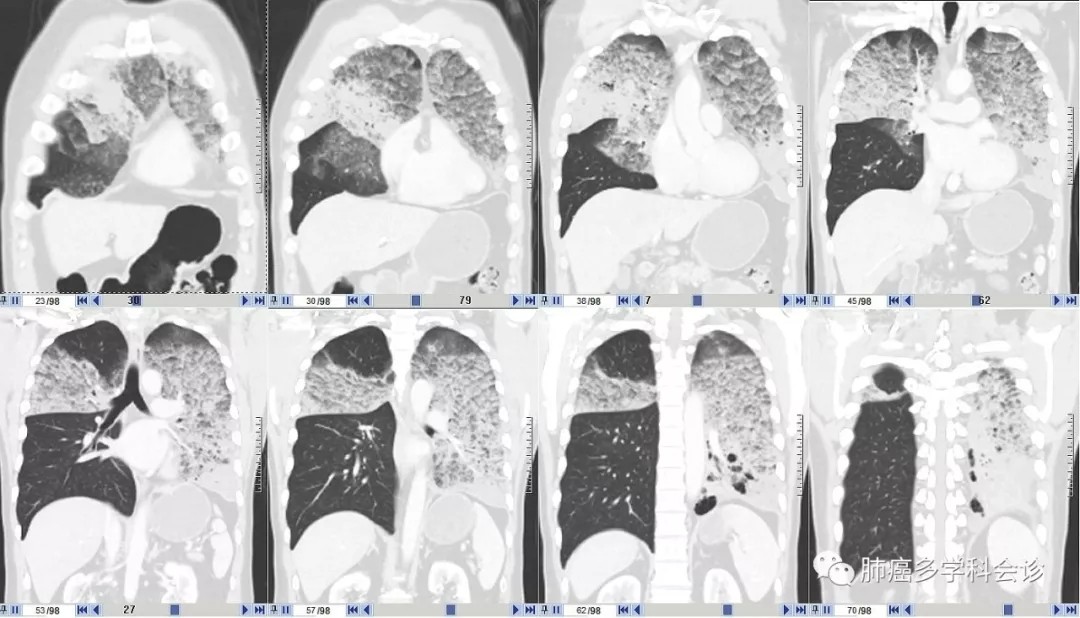

这种 CT影像符合过去的“肺泡细胞癌”特征,大量白色稀薄泡沫痰也是其特征之一,最初的病理也考虑这一诊断。但再次活检的病理诊断:粘液腺癌,并发生了 K-ras基因突变。

患者周围血白细胞、CRP和降钙素原都不高,也没有发热,与几年前肺部CT影像特征较一致,只是肿瘤组织占领的范围明显扩大,能够排除肺部感染。临床上需要与肺部的特殊感染做鉴别。

该患者的疾病进展相对缓慢,很可能更早就发病,直到4年前才引起症状,机体逐渐适应了肺被肿瘤组织占领、缺氧的状态,长期缺氧致使 Hb高达173g/L,红细胞压积高于正常范围上限。血压升高也可能与缺氧有一定关系(类似于高原性高血压)。